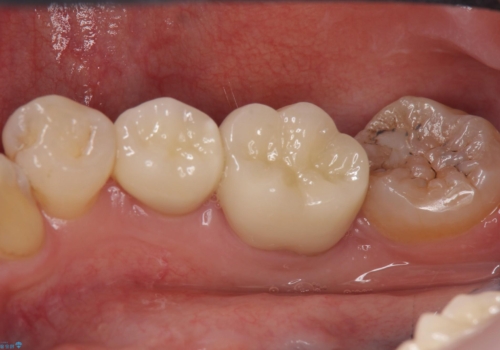

詰め物の下が虫歯 つぎはぎの歯をしっかり治療

虫歯をしっかりとった後、セラミックで修復しました。

- 24.2万円 ジルコニアクラウン、仮歯費用は治療当時の料金となります

詰め物の下の虫歯は特に奥歯は大きかったのですが、神経を取らずに済みました。